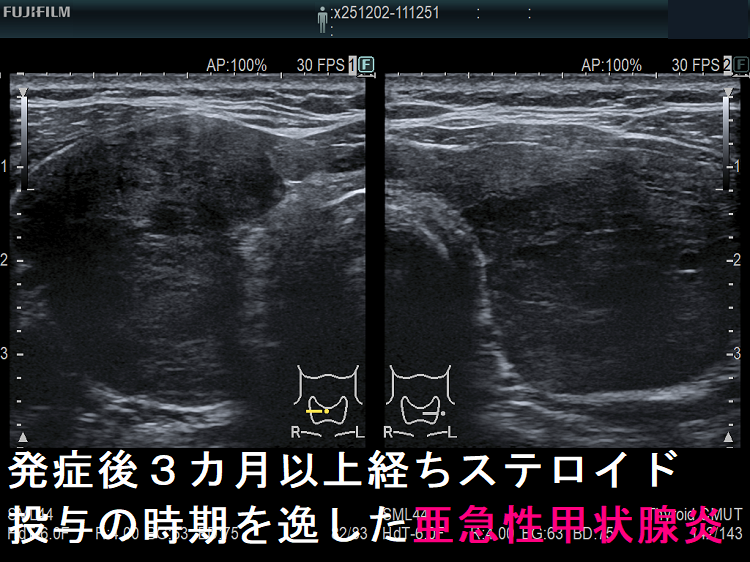

亜急性甲状腺炎には副腎皮質ホルモン剤(ステロイド剤)が劇的に効きます。たいてい服薬開始後2-3日で痛みも消え、熱も下がり、治ったような錯覚に陥ります。これにだまされ、服薬中止すれば(患者の自己判断・治療経験のない医者)、1週間以内に元の症状に戻り、最初から副腎皮質ホルモン剤(ステロイド剤)投与をやり直さねばなりません。最善の方法は、エコー所見が改善しているか確認しながら副腎皮質ホルモン剤(ステロイド剤)をゆっくり着実に減量するやり方です。(平均3-4か月は掛かります。)

- 発症後数か月以上経ち、ステロイド投与の時期を逸した場合